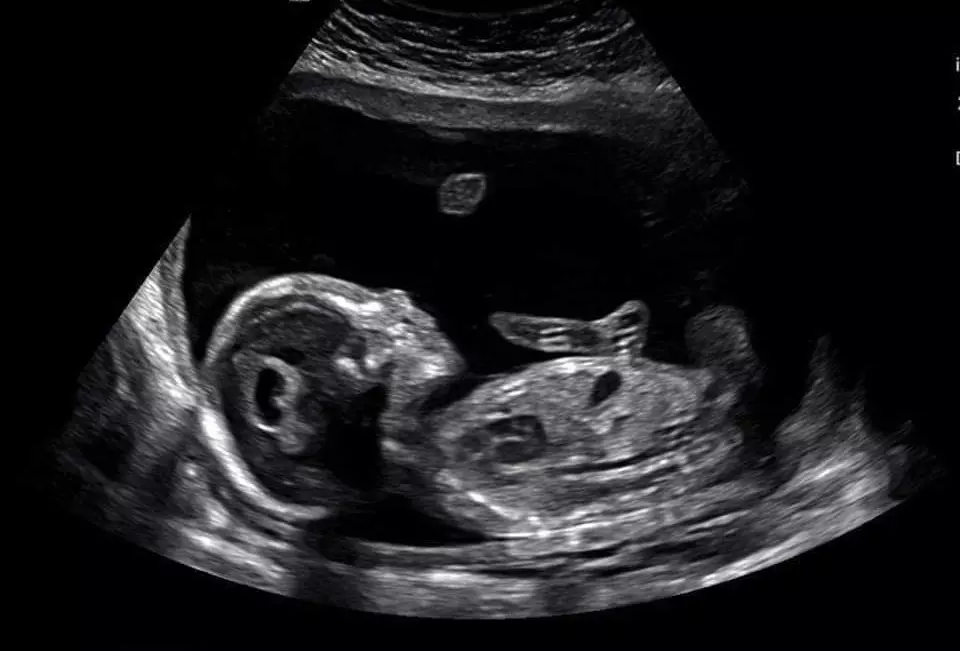

After an hour-long ultrasound of watching our beautiful son wiggle and kick on the monitor, the doctor came in and spoke words that would change our entire world in a matter of minutes.

We were told that our precious son, Zion Alexander, has severe brain and heart defects, in addition to other markers that led them to believe he has Trisomy 18. They said they do not think he will make it to term, and that if he does he will likely pass away right after birth.